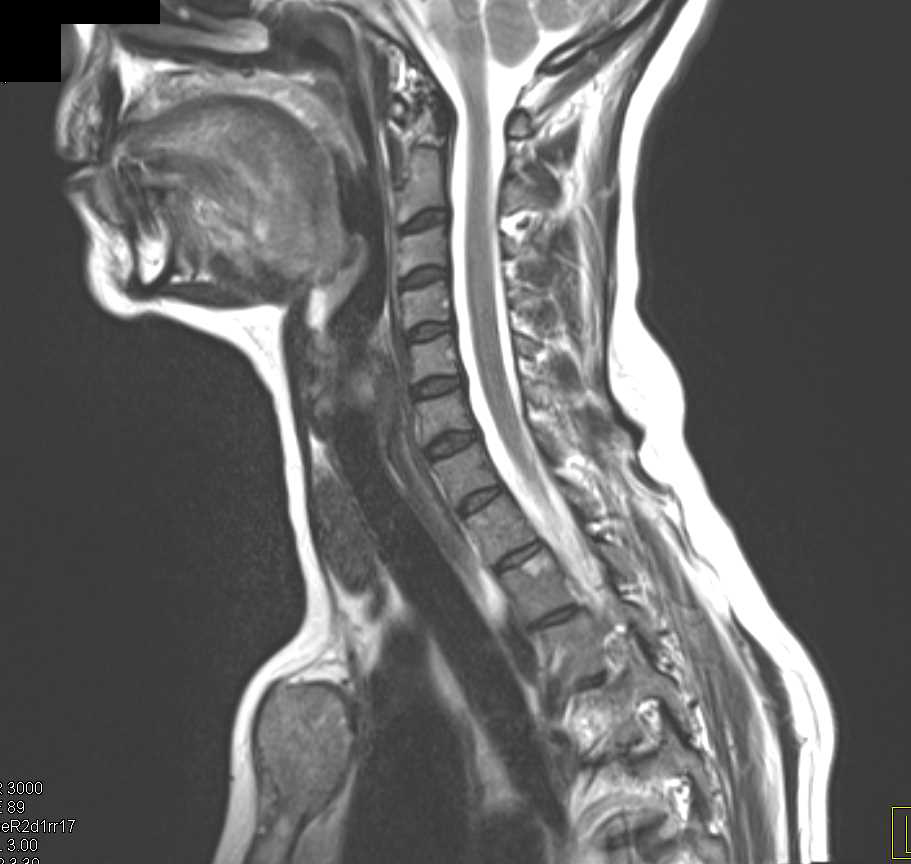

Transitional Cell Carcinoma Right Renal Pelvis